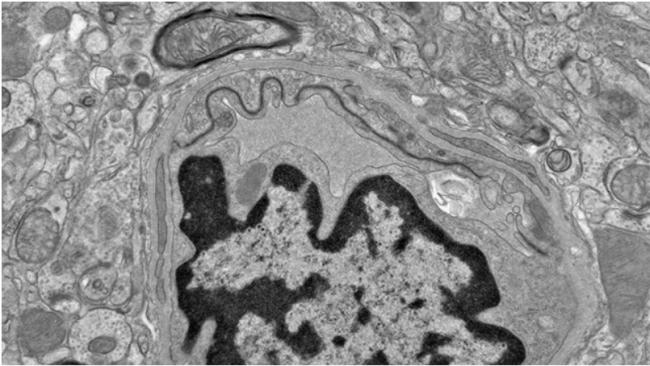

在后续实验中,研究人员利用人源脑微血管内皮细胞(构成血脑屏障的关键细胞)进行测试,结果显示DHA并未干扰修复过程。

此外,研究人员还发现,在小鼠体内,EPA对血管稳定性的破坏,可能导致与神经退行性疾病相关的有毒tau蛋白积累。

研究团队进一步分析发现,在患有慢性创伤性脑病(CTE)的人类脑组织中,也存在类似的代谢紊乱和血管损伤现象。该疾病通常与反复头部撞击有关。